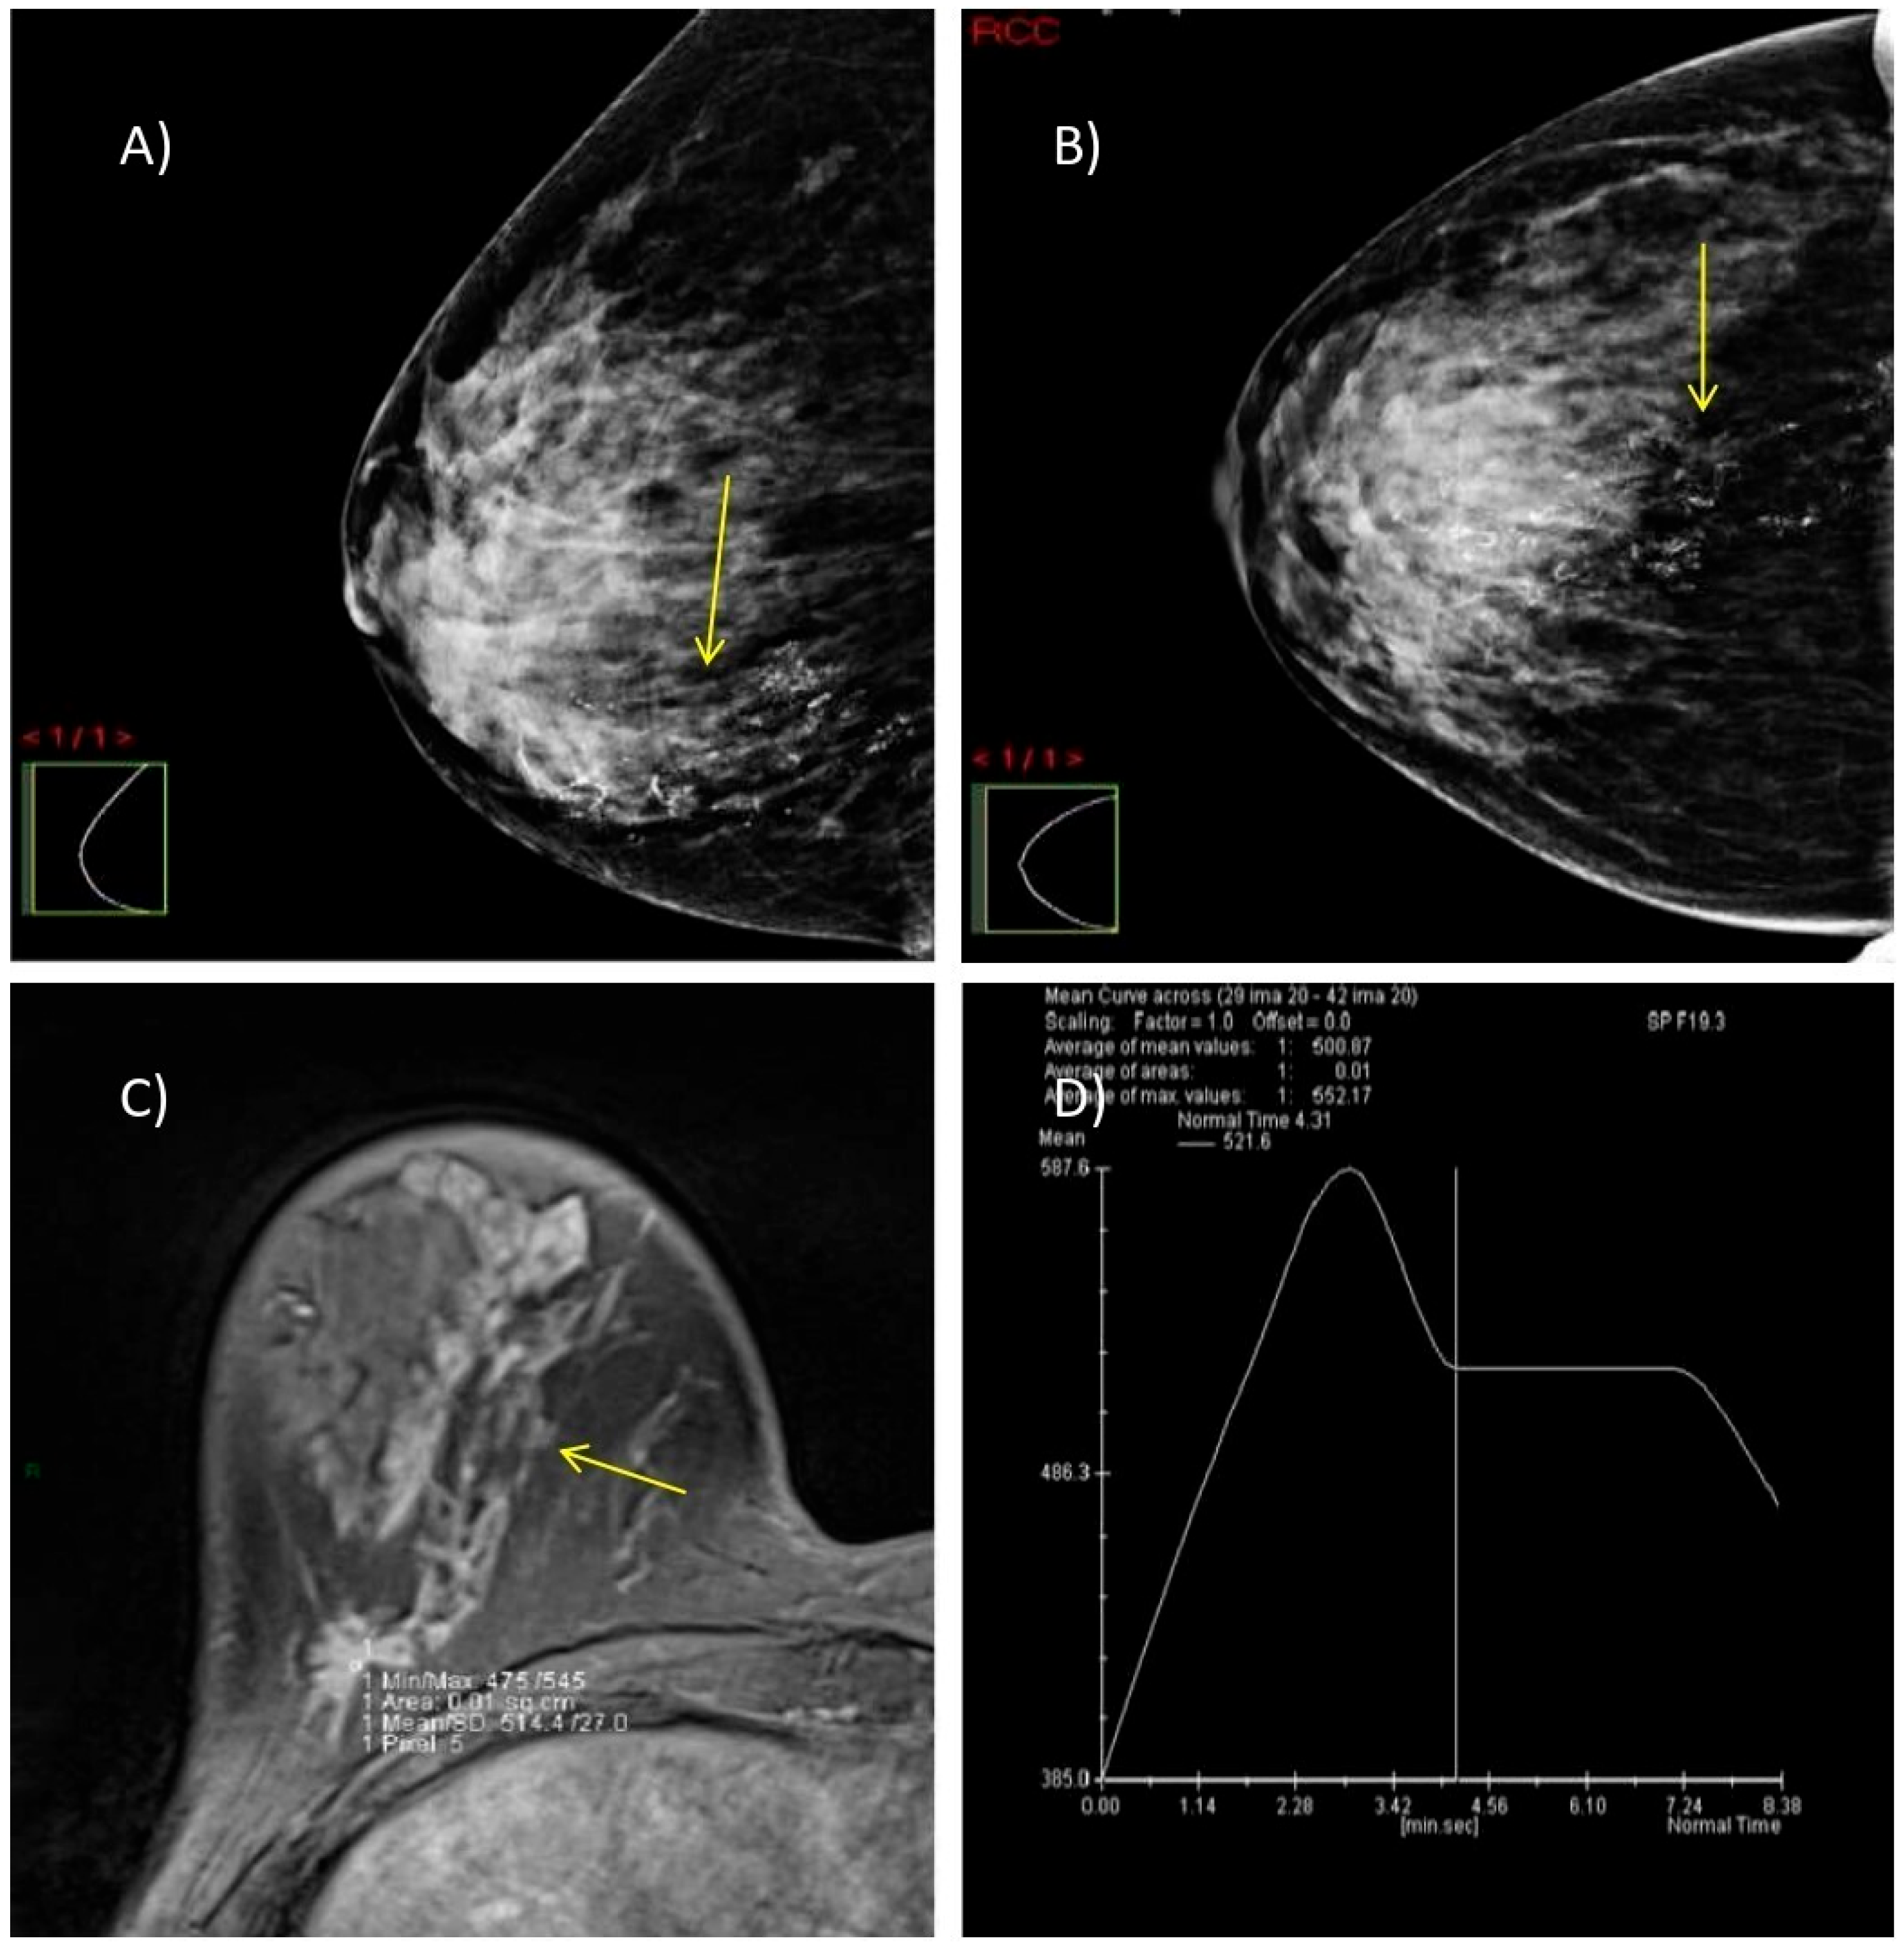

We present two illustrative cases from our female patient cohort, each with HPE-confirmed diagnosis in dense breasts. These lesions were identified using MRI, DM, and DBT, as demonstrated in Figure 5 and Figure 6.

Figure 5.

A case of a 47-year-old woman with dense breasts (ACR category C) and HPE-verified multifocal invasive ductal carcinoma, grade 2 in the right breast. (A,B) DM in MLO and CC projections shows highly suspicious microcalcifications with segmental distribution at the junction of the lower breast quadrants (yellow arrow). (C) Axial 3D T1-weighted FLASH fat-suppressed MR image demonstrates an extensive post-contrast hyperintense mass lesion extending from the nipple to the prepectoral space (yellow arrow). (D) MRI dynamic contrast enhancement curve type III (“wash out” curve).